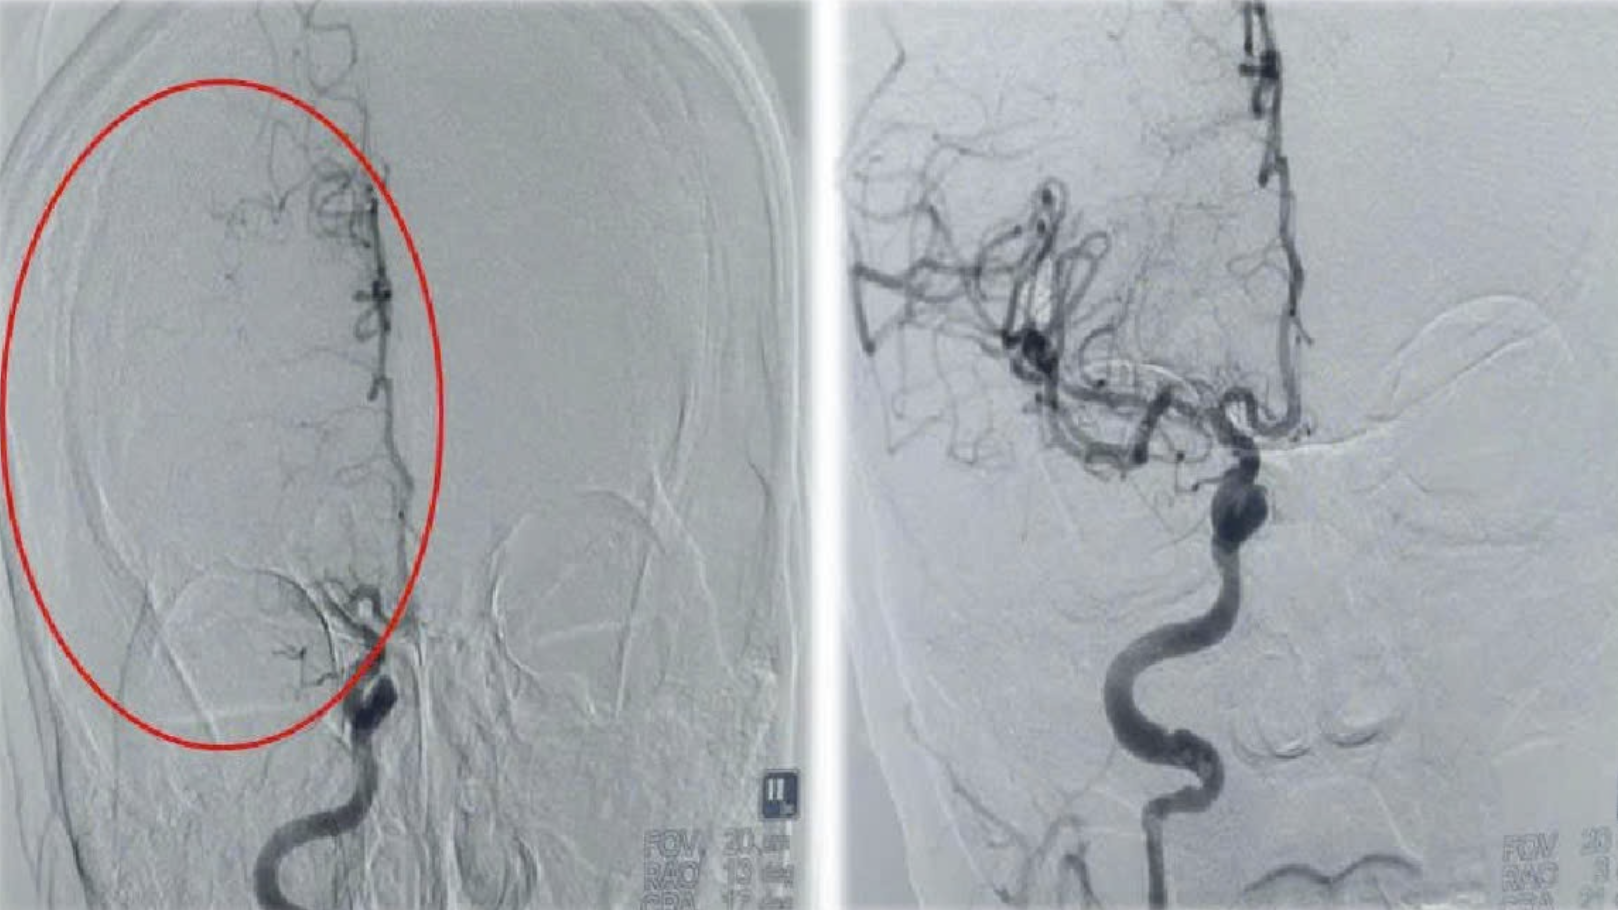

Bác sĩ Trung tâm Đột quỵ chẩn đoán đây là trường hợp đột quỵ nhồi máu não không rõ thời điểm, tuy nhiên vẫn có thể cứu được vùng não tổn thương nếu can thiệp cấp cứu kịp thời. Lập tức, người bệnh được chỉ định can thiệp lấy huyết khối (cục máu đông) ra khỏi mạch não dựa trên hệ thống chụp DSA số hóa xóa nền.

Ca can thiệp gặp nhiều khó khăn do mạch máu của người bệnh có nhiều điểm bất thường, đoạn tắc dài có nguy cơ đứt từng đoạn gây nhồi máu những vị trí khác. Sau 40 phút, ê-kíp can thiệp lấy thành công cục máu đông dài gần 10 cm như "con giun" ra khỏi mạch máu, giúp tái thông mạch máu não cho người bệnh.

Bác sĩ chuyên khoa I Nguyễn Anh Minh, Trung tâm Đột quỵ, Bệnh viện Đa khoa tỉnh Phú Thọ, cho biết đây là cục máu đông có độ dài lớn nhất mà bác sĩ trung tâm này từng can thiệp lấy ra.